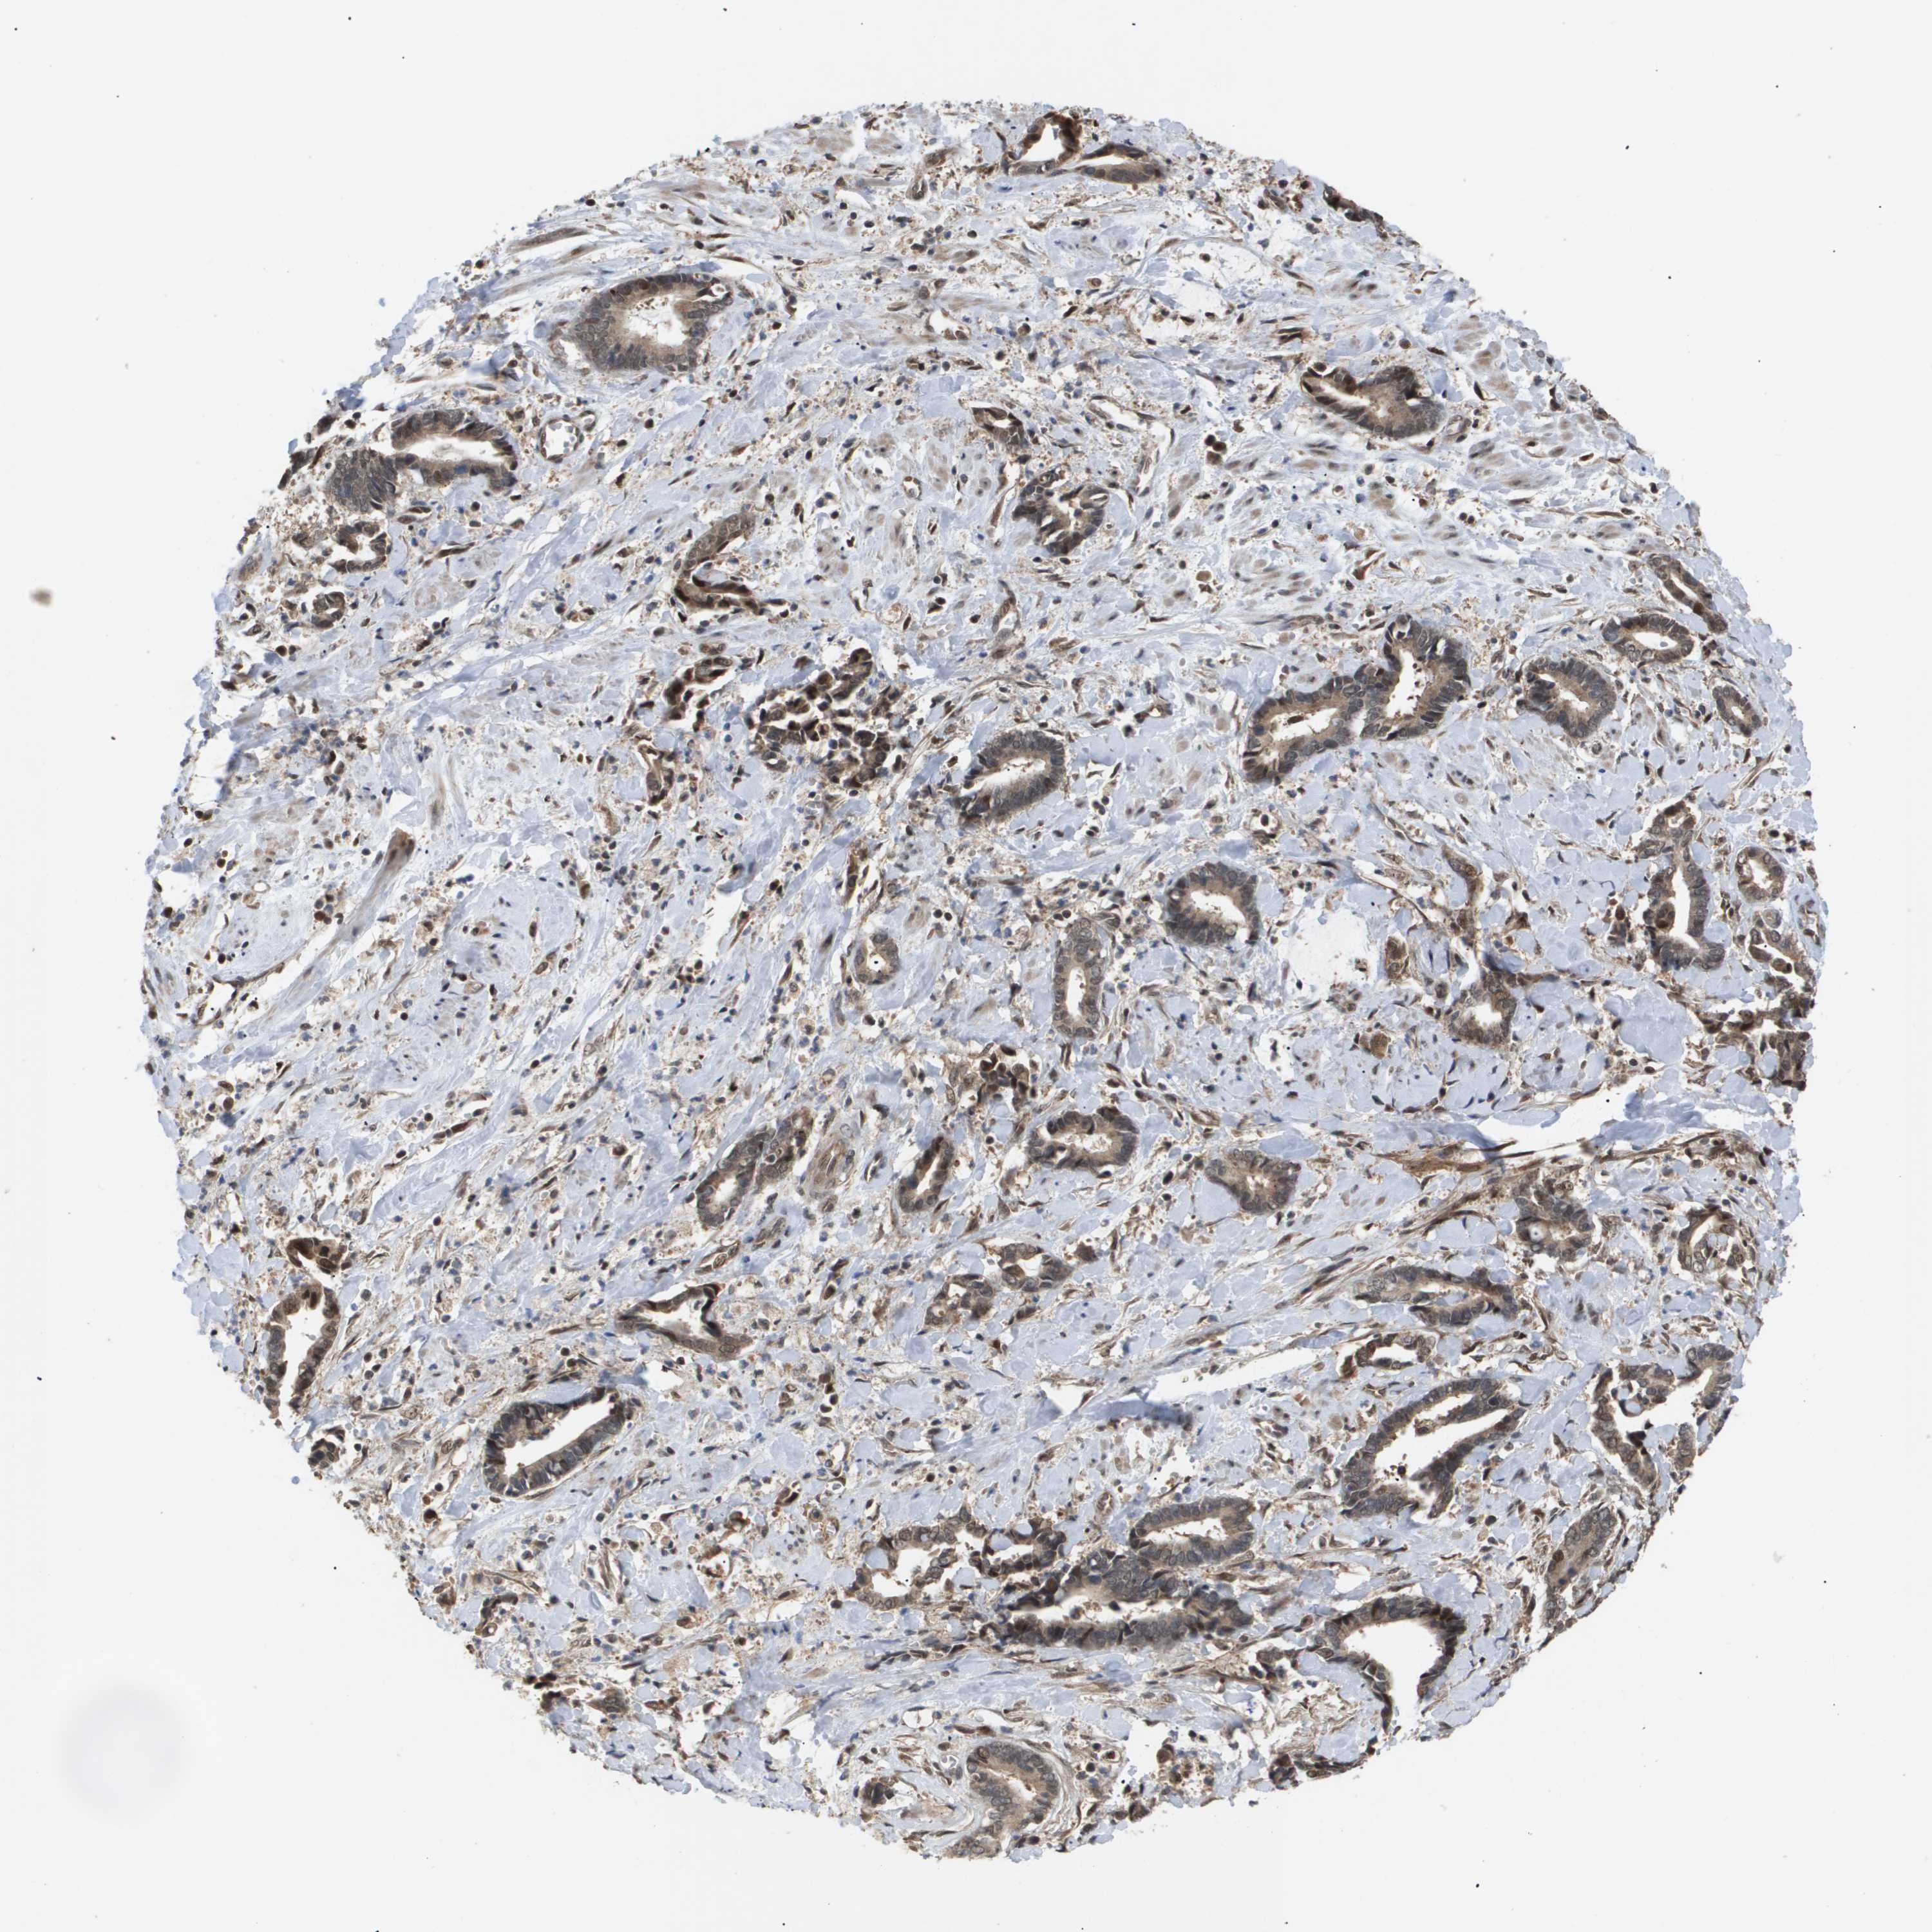

CERVICAL CANCER - Protein expressioni

A mouse-over function shows sample information and annotation data. Click on an image to view it in a full screen mode. Samples can be filtered based on level of antibody staining by selecting one or several of the following categories: high, medium, low and not detected. The assay and annotation is described here.

Note that samples used for immunohistochemistry by the Human Protein Atlas do not correspond to samples in the TCGA dataset.

Antibody stainingi

Antibody staining in the annotated cell types in the current human tissue is reported as not detected, low, medium, or high, based on conventional immunohistochemistry profiling in selected tissues. This score is based on the combination of the staining intensity and fraction of stained cells.

Each image is clickable and will lead to virtual microscopy that enables deeper exploration of all samples and also displays staining intensity scores, fraction scores and subcellular localization as well as patient and tissue information for each sample.

Antibody HPA011972

Antibody CAB011604

Antibody CAB018341

Staining

High

Medium

Low

Not detected

Intensity

Strong

Moderate

Weak

Negative

Quantity

>75%

75%-25%

<25%

None

Location

Nuclear

Cytoplasmic/membranous

Cytoplasmic/membranous,nuclear

Squamous cell carcinoma, NOS

Adenocarcinoma, NOS